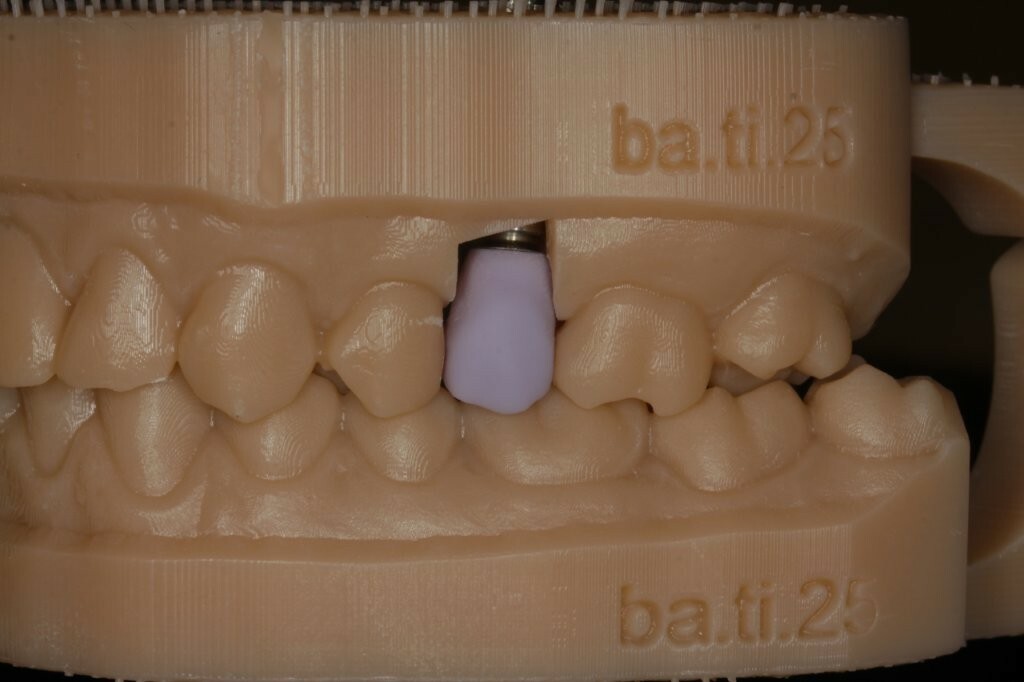

Nach Entfernung des Gingivaformers (Abb. 5) wurde ein Scan-Body (NT-Trading) eingesetzt, um die klinische Situation mit dem Intraoralscanner (Trios3 Move, 3Shape) digital abzubilden (Abb. 6). Die Vollkeramikkrone wurde auf einem gedruckten Arbeitsmodell gefertigt (Abb. 7) und die Okklusion mit Hilfe eines ebenfalls digital erstellten Gegenkiefers im gedruckten Artikulator überprüft (xSNAP, xWERK) (Abb. 8).

Nach der Anprobe des Grünlings (IPS e.max CAD, Ivoclar Vivadent) auf dem Modell wurde die Krone individualisiert und gemäß den Vorgaben des Keramikherstellers gebrannt (Abb. 9-11).